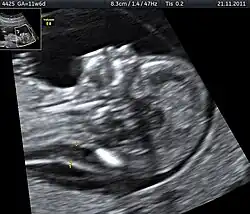

Die Messung der Nackentransparenz kann zwischen 11+0 und 13+6 Schwangerschaftswochen per Ultraschall vorgenommen werden (bzw. bis zu einer Scheitel-Steiß-Länge des Kindes von max. 84 mm); die besten Ergebnisse werden erzielt, wenn die Untersuchung mit 12 Schwangerschaftswochen durchgeführt wird. Ob der Ultraschall vaginal (über die Scheide) oder transabdominal (über die Bauchdecke) gemacht wird, ist dabei egal, denn die Ergebnisse unterscheiden sich nicht wesentlich. Der Untersuchungsablauf unterscheidet sich für die Schwangere nicht von sonstigen Ultraschalluntersuchungen und ist nach heutigem Wissensstand weder für die Schwangere noch für das ungeborene Kind schädlich.

Zur Berechnung der Ausprägung der Nackentransparenz wird das Ungeborene im Sagittalschnitt, d. h. in der Seitenansicht mit Messansatz parallel zur Mittelachse, per Ultraschall dargestellt. Das Baby sollte möglichst den gesamten Ultraschallmonitor ausfüllen, seine Wirbelsäule sollte unten liegen und sein Kopf darf sich weder in der Flexionsposition noch in der Hyperextensionsstellung befinden.